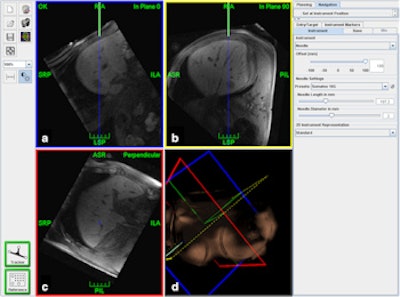

Screenshot of the navigation scene. Reformatted MR images of the planning dataset are interactively shown either instrument-related inplane (a), 90° in-plane (b) or perpendicular to the instrument (c). On a and b, the green lines indicate the needle in full length and the blue lines show its trajectory to facilitate orientation to the target (arrow head). For better orientation, a 3D reconstruction is also provided (d).